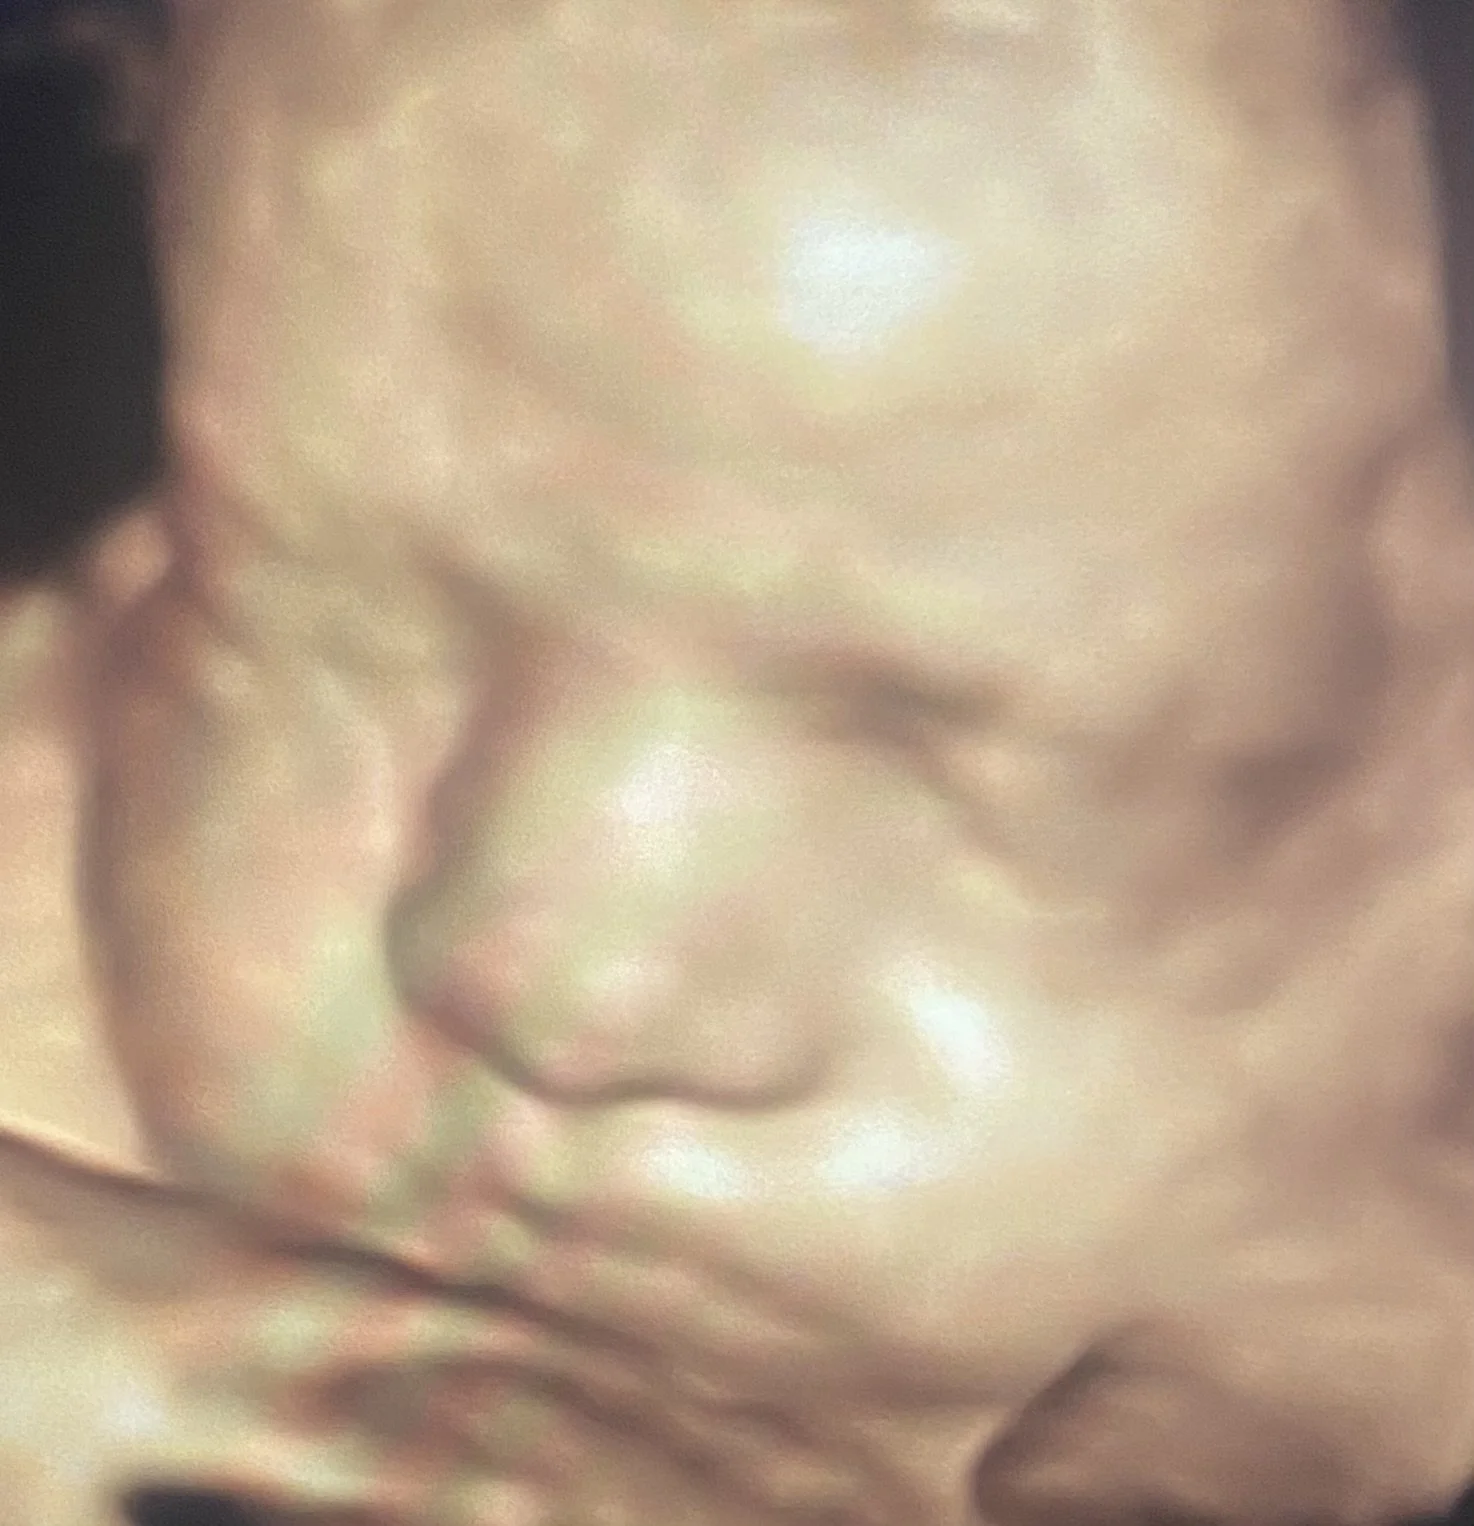

Our state-of-the-art technology (GE Voluson Swift) is one of the most popular ultrasound machines for obstetric scanning. It features class leading 4D imaging as well as proprietary GE efficiency technologies. 3D/4D imaging modes, CrossXBeam and Speckle Reduction imaging assist with excellent accuracy.

ScanSanctuary Client Scan Examples